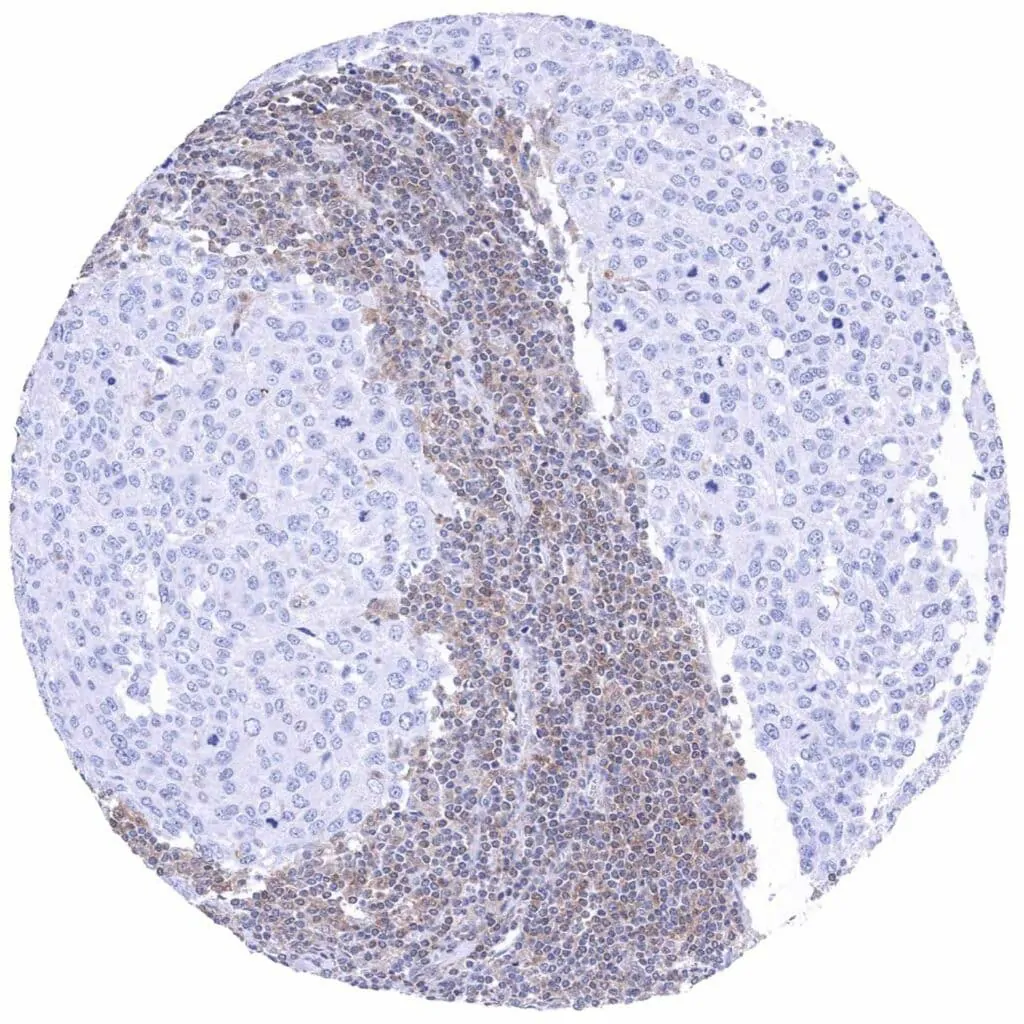

Lymph node – Hodgkin's lymphoma with complete absence of MTAP staining in tumor cells. Intense MTAP staining of associated non-neoplassic cells.

Lymph node – Hodgkin's lymphoma with complete absence of MTAP staining in tumor cells. Intense MTAP staining of associated non-neoplassic cells